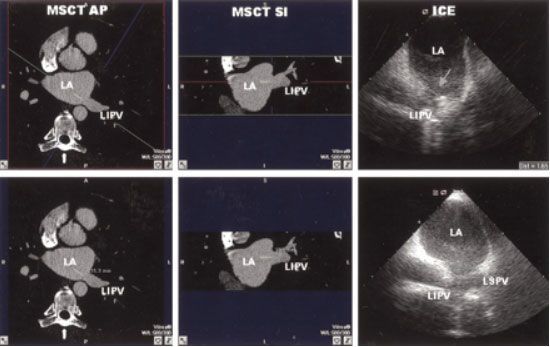

Monique R.M. et al. (2005) опубликовали результаты прямого сравнения трансторакальной ЭХОКГ и МСКТ у 42 пациентов перед абляцией устьев легочных вен: измеренный диаметр устьев легочных вен был сопоставим, но при МСКТ отмечена выше частота выявления добавочных ветвей легочных артерий [65].

![]() |

| Рис.36. Измерения левой нижней легочной вены (LIPV) при МСКТ (слева) и при трансторакальной ЭХОКГ (справа). LA-левое предсердие. LSPV –левая верхняя легочная вена. |